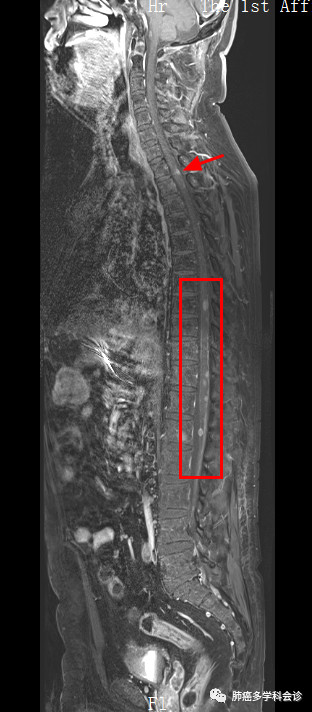

随后做核磁共振检查,发现全脊髓脊膜多发转移,下图展示了全脊髓内的多发转移灶,转移灶表现为脊髓内的白色小点:

我们再把上图的局部进行放大,以更好显示转移灶: